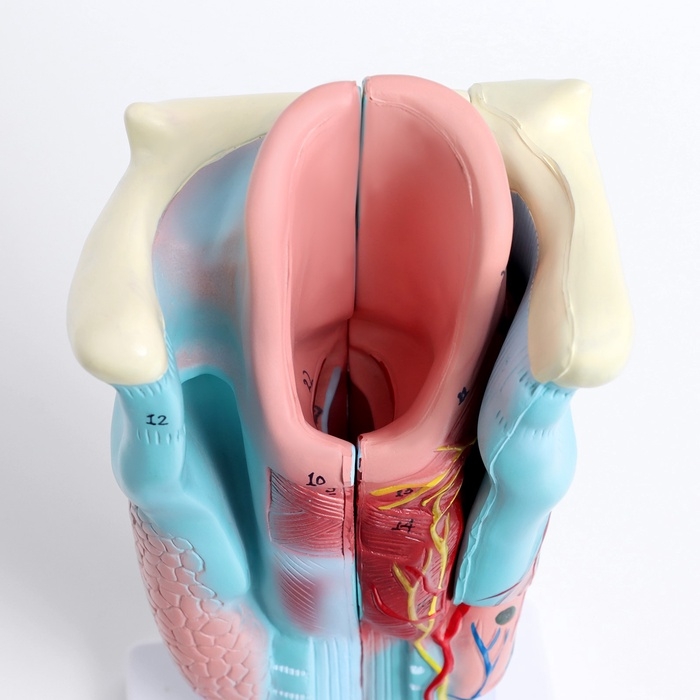

ЕКБ 41

No Brand, артикул: 7072360